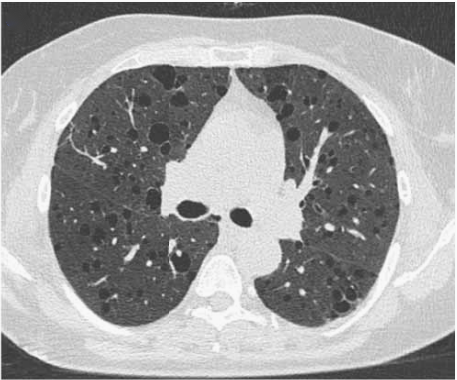

LAM的HRCT有典型的特征性改变,主要表现为双肺弥漫性薄壁囊性改变(图3)。囊性病变的直径在数毫米至数厘米。其他发现包括磨玻璃影、小叶间隔增厚、气胸和胸腔积液。

图3 散发性LAM患者的HRCT显示多个双侧分布的数厘米的薄壁囊肿